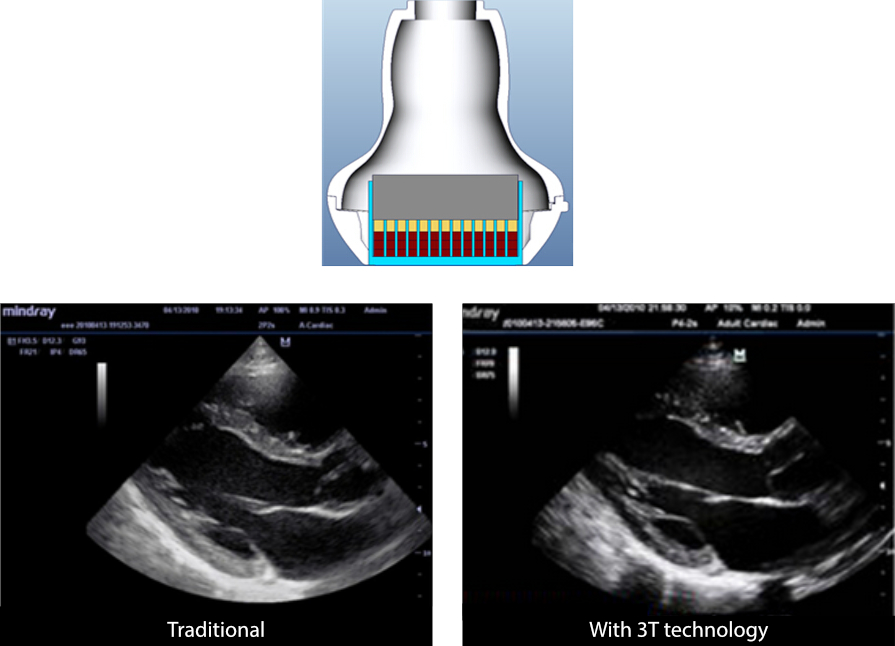

3T Transducer Technology?

MindrayŌĆÖs patented transducer technology increases image bandwidth and transmission efficiency:

- Triple-matching layer design for higher sensitivity, wider bandwidth, and improved S/N

- Total-cut design for lower cross-talk noise, higher accuracy, and improved lateral resolution

- Thermal-control design for better acoustic transmission